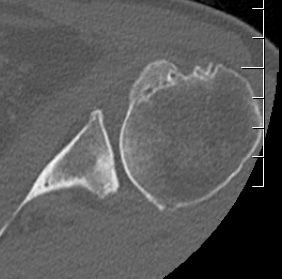

X-ray

Typical changes of OA

1. Teardrop / beard osteophytes on inferior head & glenoid

2. Osteochondral loose bodies

Beard osteophytes

Osteochondral loose body